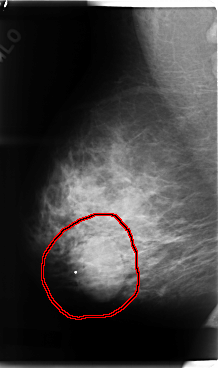

C_0076_1.RIGHT_CC

RIGHT_CC LINES 4776 PIXELS_PER_LINE 2776 BITS_PER_PIXEL 12 RESOLUTION 50 OVERLAY

FILE: C_0076_1.RIGHT_CC.OVERLAY

TOTAL_ABNORMALITIES 1

ABNORMALITY 1

LESION_TYPE MASS SHAPE LOBULATED MARGINS MICROLOBULATED

ASSESSMENT 4

SUBTLETY 5

PATHOLOGY MALIGNANT

TOTAL_OUTLINES 1

BOUNDARY